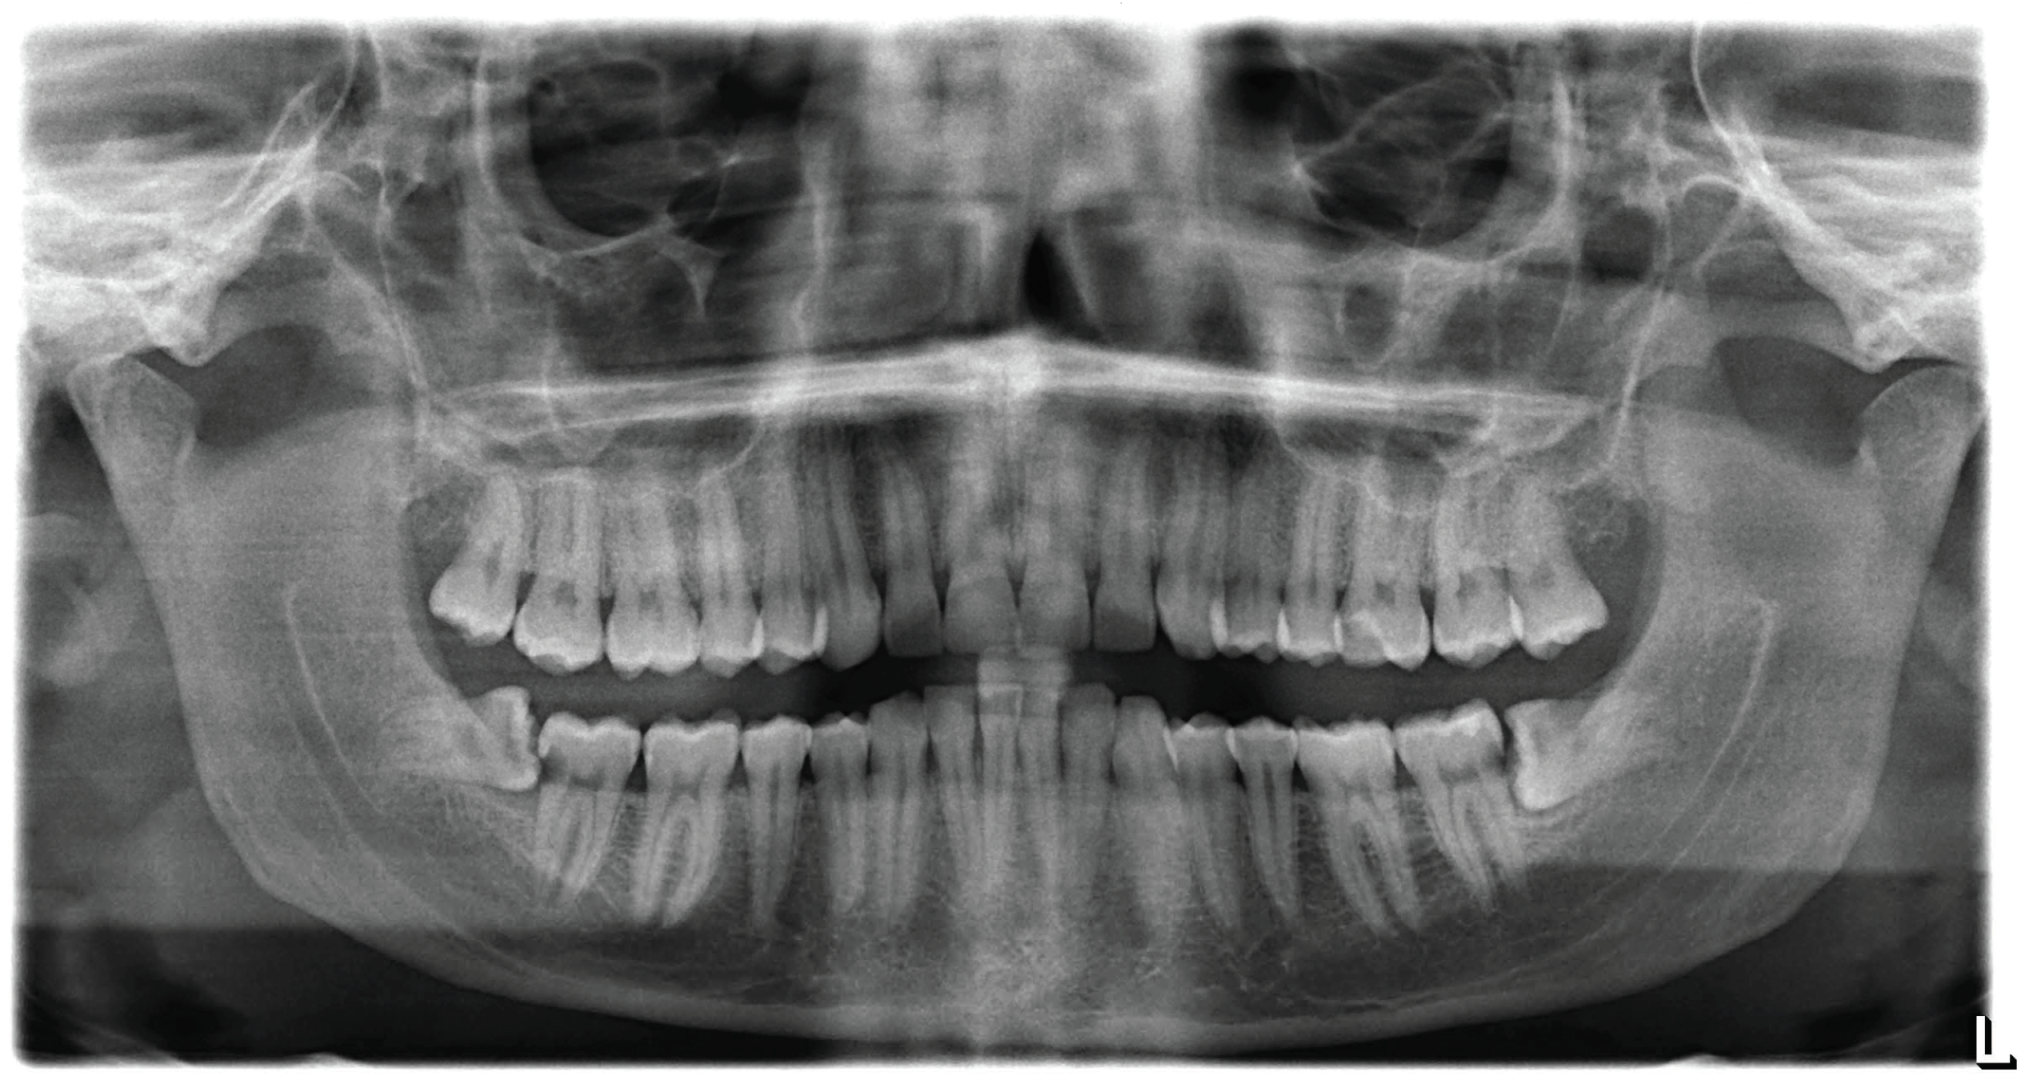

The patient showed up to our clinic with complaints following a wisdom tooth extraction. Periapical and panoramic radiographs (Figure 1) pointed to a mesially inclined and impacted tooth #38 having been recently extracted, which had caused caries in the distal portion of the adjacent tooth (tooth #37). A similar situation was observed on the opposite side; however, in that case, the wisdom tooth extraction had not led to any negative consequences. The extraction procedure was performed in March 2022, and lasted approximately two and a half hours. At the end of the procedure, the dentist took a post-operative dental radiograph (Figure 2) and informed the patient that a root fragment had not been removed. The dentist recommended a Cone-Beam CT scan to determine the fragment’s position. Following the dentist’s advice, the patient underwent a Cone-Beam CT scan at a medical center in March. On the same day, the patient returned to the dentist with the results, which showed that the root fragment had been displaced into the submandibular space (Figure 3), further necessitating a removal procedure at a hospital facility. The patient reported undergoing antibiotic and anti-inflammatory therapies for pain management and lowering the risk of infections prior to the surgery. In April 2022, the patient was admitted to the dentistry unit of a hospital where urgent maxillofacial surgery was deemed necessary. The patient was advised to consult a maxillofacial surgery specialist, who emphasized the importance of timely intervention to control the existing infection and prevent further complications caused by the dislocated root. Subsequently, the patient went to a private clinic, where a maxillofacial surgeon and their team performed the extraction of the dental root under both general and local anesthesia, as documented in the medical records provided to the patient. The procedure required a one-day hospital stay. Upon discharge, the patient was prescribed a supportive pharmacological therapy, including non-steroidal anti-inflammatory drugs (ibuprofen in a dosage of 400 mg every 4–6 h) and an antibiotic (amoxicillin with clavulanic acid in a dosage of 875 mg + 125 mg, twice daily for 5 days), as noted in the medical records.

Dental radiographs and cone-beam computer tomography (CBCT) revealed a dislocation, of what was likely the mesial root of a tooth, into the left submandibular space. No other pathologies related to current symptoms were evident and there were no lesions requiring dental intervention.

Figure 3. CBCT sagittal and axial views showing the position of the residual fractured root outside the bone in the submandibular space.